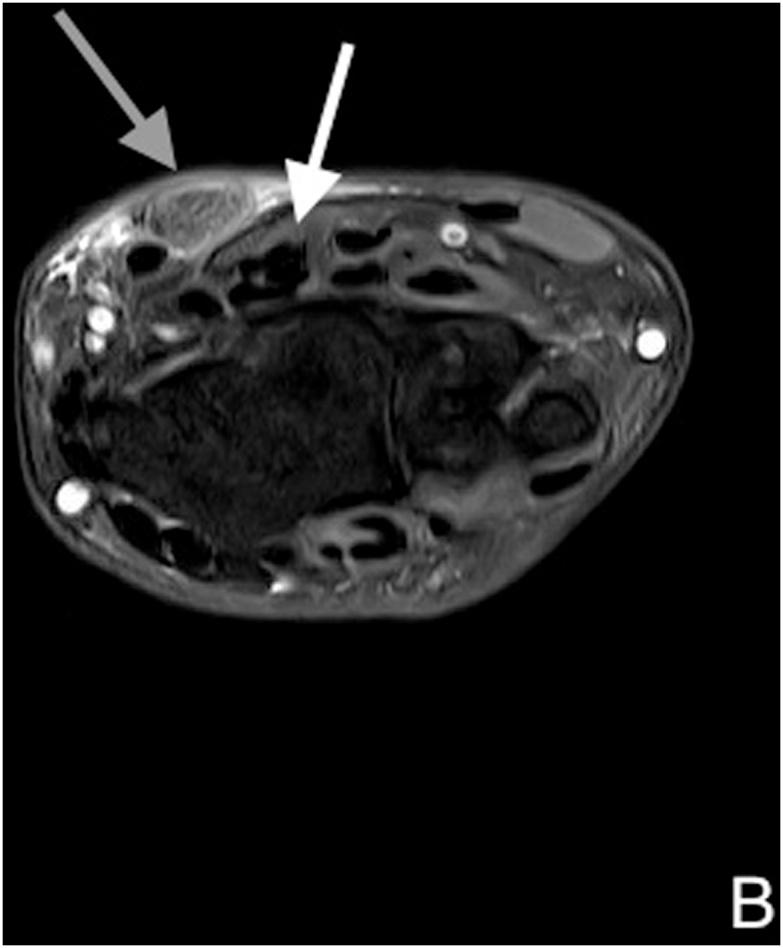

A 52-year-old woman presenting with previous rupture of the palmaris longus tendon. During surgery, we found that the end of the tendon had formed nodules. After removing the nodules, the PCBMN was released, and half a year later, the abnormal feelings had disappeared.